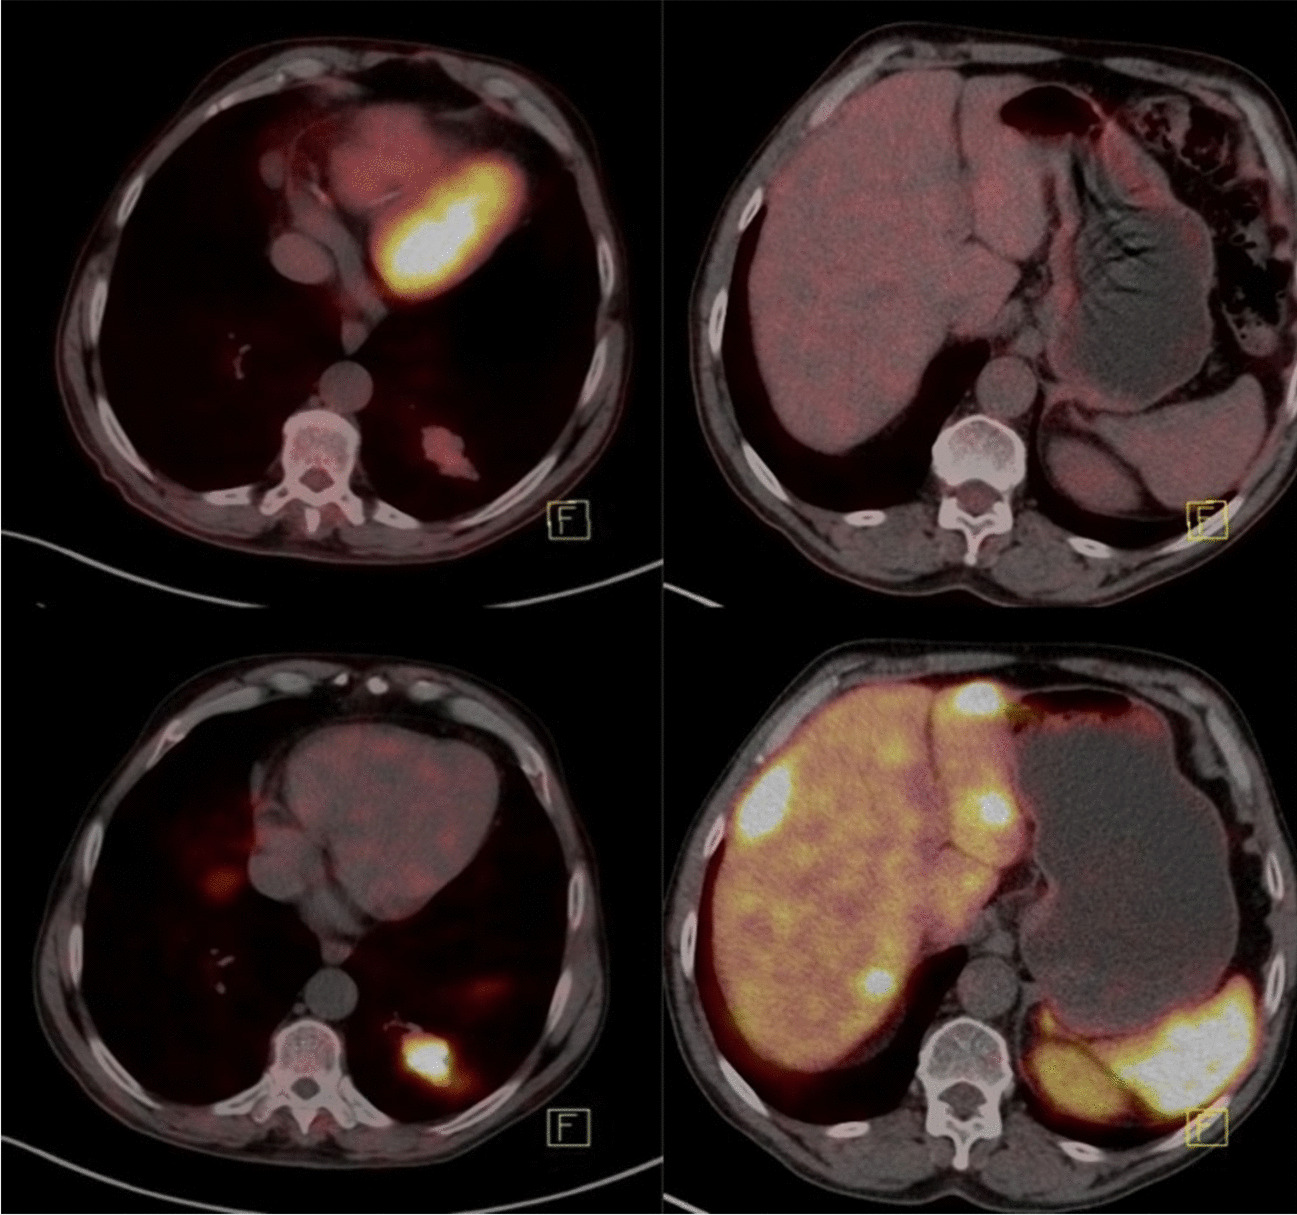

Initial Staging of Lung Cancer with FDG PET/CT

Lung cancer is one of the leading causes of cancer death in industrialized nations, regardless of gender. Accurate staging...

Current Pulmonology Reports